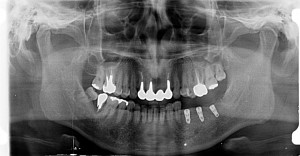

こちらの患者さんは長年歯を入れなかった為に、上の歯が伸びてきています。左下にインプラントを埋入しましたが、このままではインプラントの上部構造を入れるスペースがありませんので、上の歯を削りクラウンにしなければなりません。

やはり歯を抜きっぱなしに放置すると後で余分な治療をしなければならないことになります。

それから骨は抜歯後1年で0.5mm吸収する(溶ける)と言われているので、早期にインプラントを入れて荷重することで骨の吸収を抑えることができます。オペ後6週でインプラントの頭を出して上部構造の製作に取り掛かります。